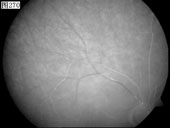

[组图]优秀眼底图片奖网上评选活动启动         ★★★

优秀眼底图片奖网上评选活动启动

优秀眼底图片奖应征作品展示